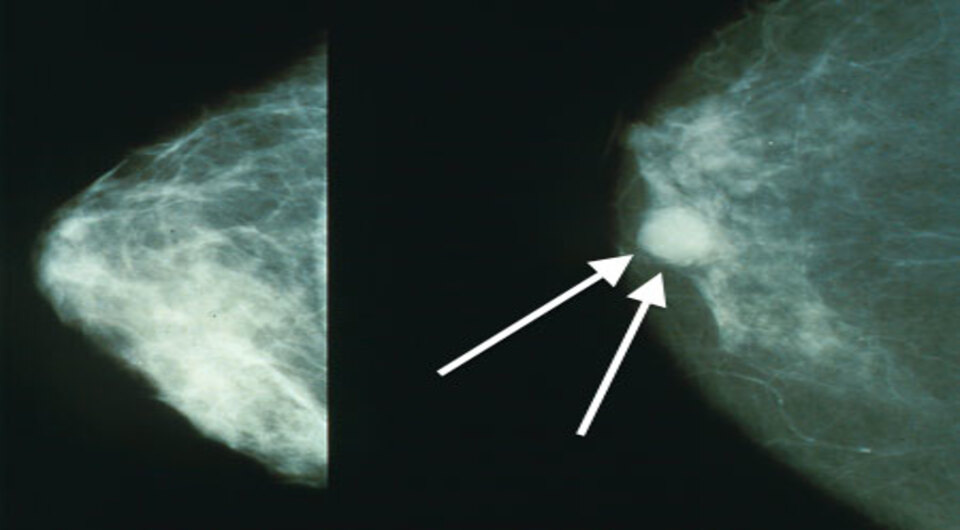

Bakerstmd / Wikimedia Commons / CC-BY-SA-4.0

Кэти О'Брайен (Katie O’Brien) с коллегами из Национального института окружающей среды и здоровья проанализировала данные 459476 женщин возрастом от 16 до 54 лет за 8 лет наблюдений. Оказалось, что у тех, которые использовали эстроген-гестагенные гормональные препараты, риск развития рака груди до 55 лет был на 10 процентов выше, чем у женщин, которые гормональную терапию не принимали. У некоторых категорий риск был еще выше: у женщин, принимавших такую комбинацию более двух лет (на 18 процентов выше) и у женщин, которым не удаляли матку и яичники (на 15 процентов выше). Статья опубликована в The Lancet Oncology.